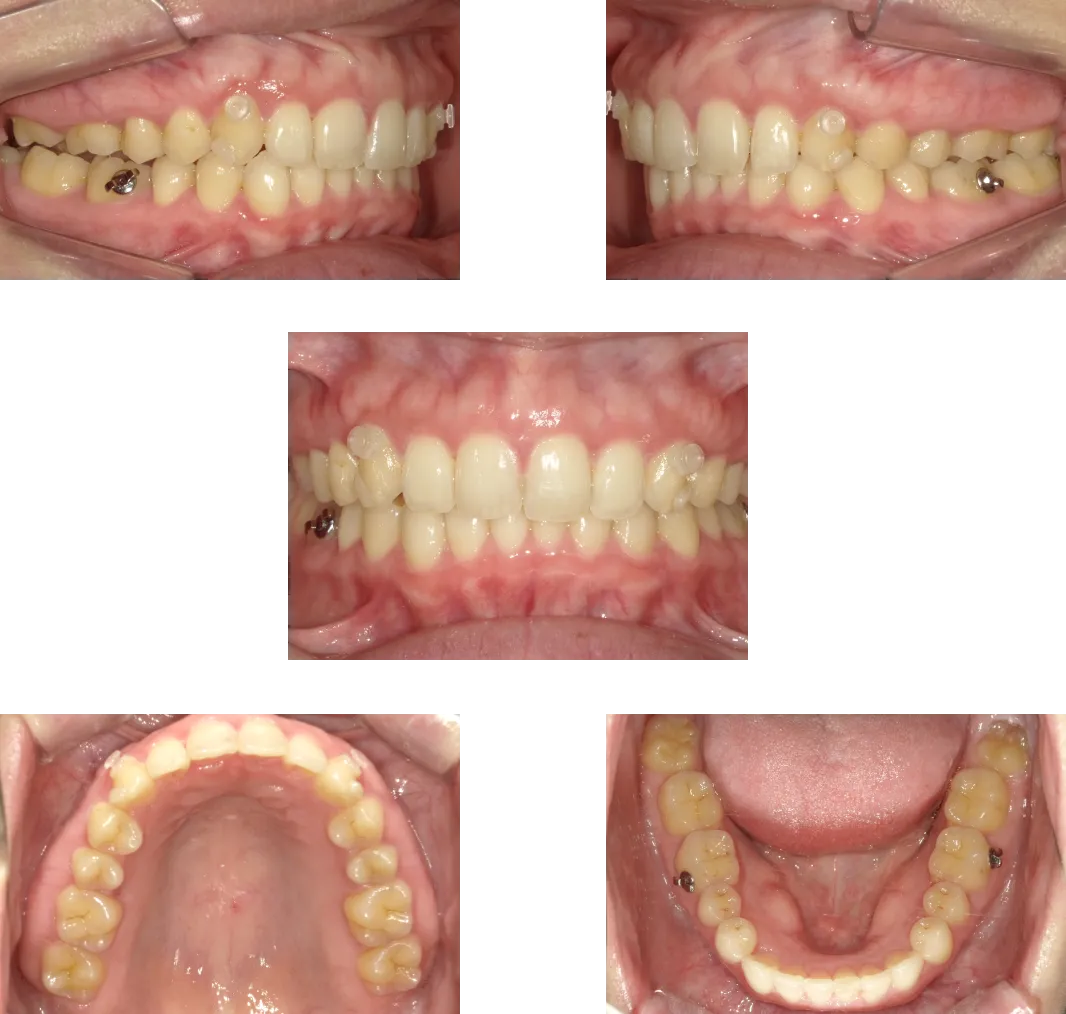

過蓋咬合 -20歳-

• Before

• After

診断

叢生、骨格性上顎前突

治療期間

1年6ヶ月+保定期間2年

料金

1,070,000円

抜歯

なし

リスク

痛み、軽度の歯根吸収、術後の変化